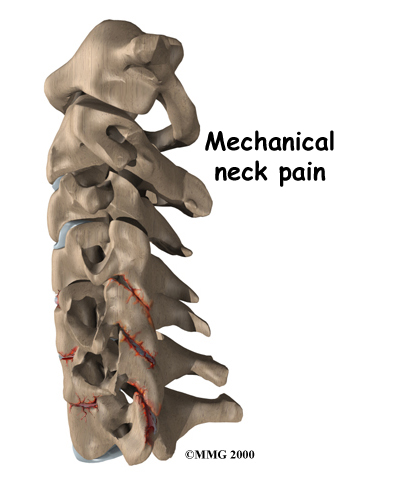

Mechanical Neck Pain

Mechanical neck pain is caused by wear and tear on the parts of the neck. It is similar in nature to a machine that begins to wear out. Mechanical pain usually starts from degenerative changes in the disc. As the disc starts to collapse, the space between the vertebrae narrows, and the facet joints may become inflamed. The pain is usually chronic. (Chronic pain builds over time and is long-lasting.) The pain is typically felt in the neck, but it may spread from the neck into the upper back or to the outside of the shoulder. Mechanical neck pain usually doesn't cause weakness or numbness in the arm or hand, because the problem is not from pressure on the spinal nerves.

Mechanical neck pain is caused by wear and tear on the parts of the neck. It is similar in nature to a machine that begins to wear out. Mechanical pain usually starts from degenerative changes in the disc. As the disc starts to collapse, the space between the vertebrae narrows, and the facet joints may become inflamed. The pain is usually chronic. (Chronic pain builds over time and is long-lasting.) The pain is typically felt in the neck, but it may spread from the neck into the upper back or to the outside of the shoulder. Mechanical neck pain usually doesn't cause weakness or numbness in the arm or hand, because the problem is not from pressure on the spinal nerves.